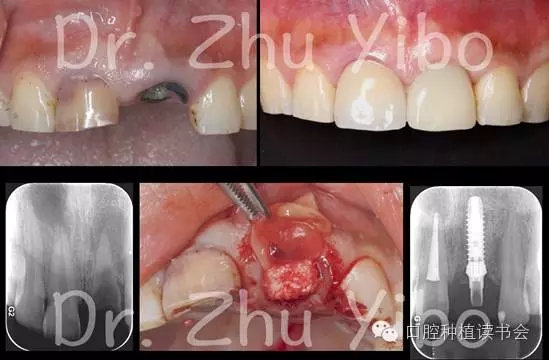

口腔種植讀書會是由國內(nèi)著名院校的中青年學(xué)者發(fā)起成立的公益性學(xué)術(shù)組織。“公益、分享、進步”是口腔種植讀書會成立的愿景,通過對國際權(quán)威口腔種植學(xué)著作及文獻的出版與推廣,結(jié)合臨床案例與科研進展,秉承“嚴(yán)謹(jǐn)、求實、循證”的理念為口腔醫(yī)生與技師奉獻最新、最實用的的口腔種植知識與技術(shù),并定期推出學(xué)術(shù)著作及線上、線下公益課程,推動口腔種植事業(yè)更好的發(fā)展。Socket Shield Technique-牙根屏障即刻種植術(shù)是當(dāng)下口腔種植學(xué)界最熱門、最具爭議的技術(shù)之一。國際上應(yīng)用該技術(shù)的醫(yī)生屈指可數(shù),均為頂級的大師;國內(nèi)開始學(xué)習(xí)并實施該技術(shù)的醫(yī)生越來越多,可其中能成功實施者寥寥。于是,牙根屏障即刻種植術(shù)似乎成了霧里看花、水中望月,上下求索而不得。筆者是國內(nèi)最早關(guān)注該技術(shù)的醫(yī)生之一,曾赴慕尼黑,受訓(xùn)于牙根屏障即刻種植術(shù)創(chuàng)始人,國際頂級種植牙周大師Marc Hurzeler。并于2013年在國內(nèi)會議上首次報道了牙根屏障即刻種植術(shù)的病例,引發(fā)了強烈反響和爭議。目前筆者完成的牙根屏障即刻種植術(shù)病例數(shù)量、治療效果、病例觀察時間在國內(nèi)均處于領(lǐng)先地位。下面希望通過本文的介紹,能使大家初步了解Socket Shield Technique-牙根屏障即刻種植術(shù)的來龍去脈。21世紀(jì)初,隨著種植技術(shù)和材料的不斷發(fā)展,種植治療的適應(yīng)癥不斷擴大,國際上有學(xué)者提出了“種植無邊界”的口號,似乎種植治療無所不能。但是不久,在美學(xué)區(qū)即刻種植的病例中,出現(xiàn)了大量的美學(xué)并發(fā)癥:唇側(cè)牙齦退縮,修復(fù)基臺甚至種植體表面暴露,難以處理。于是種植醫(yī)生停止了狂熱的美學(xué)區(qū)拔牙、即刻種植治療方案,開始反思,探求美學(xué)區(qū)即刻種植失敗的原因。

拔牙后如果不做任何干預(yù),牙槽窩的唇側(cè)骨板會發(fā)生明顯的生理性改建、吸收,導(dǎo)致牙槽突的高度降低、豐滿度減少;而拔牙后在牙槽窩內(nèi)即刻植入種植體并不會阻止牙槽窩的生理性改建。至此,種植醫(yī)生終于明白了美學(xué)區(qū)即刻種植的風(fēng)險以及美學(xué)失敗的原因,對于美學(xué)區(qū)的種植治療方案分化為兩個派別。一部分專家選擇拔牙后不做任何干預(yù),自然愈合1-2個月后進行早期種植,同時做GBR術(shù)恢復(fù)牙槽突的豐滿度,取得了相當(dāng)可靠、滿意的美學(xué)效果。但是這種方案的缺點也顯而易見:手術(shù)次數(shù)多(拔牙、種植植骨、二期手術(shù)),治療周期長(10-12個月),手術(shù)創(chuàng)傷大,治療費用高。另一部分專家選擇拔牙后進行牙槽嵴保存,運用包括牙槽窩封閉、牙槽窩植骨和牙槽窩擴增等不同的技術(shù)減少牙槽窩生理性改建吸收,愈合4-6個月后進行種植,通常也可以取得不錯的美學(xué)效果。但是這種方案的缺點也很明顯:有研究表明,雖然牙槽嵴的外形得到了保存,但牙槽骨愈合的質(zhì)量不如自然愈合。另外,有些病例雖然做了牙槽嵴保存,在種植時仍需要進行GBR術(shù),這樣也大大延長了治療周期。除了以上的兩大派別,還有個少數(shù)派(說是少數(shù)派,其實就是一個人)對美學(xué)區(qū)即刻種植方案進行了更深入的思考:能不能有一種方案,可以拔牙后即刻種植(減少了手術(shù)次數(shù)),即刻修復(fù)(減少了治療周期),不用翻瓣(減少了手術(shù)創(chuàng)傷),不用植骨(減少了手術(shù)費用),還能取得長期穩(wěn)定的美學(xué)效果呢?他意識到問題的關(guān)鍵在于如何保存拔牙后牙槽窩的唇側(cè)骨板,使其不發(fā)生生理性的吸收、改建。從解剖學(xué)上分析,前牙區(qū)唇側(cè)的牙槽骨板菲薄(大多數(shù)小于0.5mm),唇側(cè)骨板牙槽嵴頂大部分為束狀骨,束狀骨通過牙周膜內(nèi)的穿通纖維,和牙根面的牙骨質(zhì)緊密相連,形成了一體的復(fù)合結(jié)構(gòu),束狀骨的血液供應(yīng)也來自于牙周膜內(nèi)的血管。當(dāng)牙根被拔除后,牙周膜被撕裂、消失,束狀骨沒有了支持,沒有了血液供應(yīng),不可避免的會發(fā)生吸收。

這時,一個天(feng)才(kuang)的想法在他的腦海中閃現(xiàn),如果拔牙時保留一部分唇側(cè)的牙根,保留唇側(cè)的牙周膜,能否保存牙槽窩唇側(cè)的束狀骨,同時不影響植入種植體的骨結(jié)合呢?這個想法是和之前所有的教科書格格不入的,一直以來老師都告訴我們,拔牙要拔干凈,殘留的牙根可能發(fā)生牙根固連、排異反應(yīng)、甚至炎癥。但是理性的思考加上瘋狂的創(chuàng)意產(chǎn)生的是偉大的結(jié)果。動物實驗獲得了成功,組織切片證實,保留唇側(cè)部分牙根、即刻種植后3個月,種植體的骨結(jié)合良好,牙根周圍沒有炎癥,更重要的是,拔牙窩唇側(cè)骨板沒有明顯的吸收、改建。之后他的臨床病例自然的也獲得了成功。這是一項了不起的美學(xué)區(qū)即刻種植技術(shù),可以通過最小的代價,獲得最完美的治療效果,但是卻非常難以推廣,成為新的即刻種植治療方案“金標(biāo)準(zhǔn)”。原因無外乎幾點:操作難度大,技術(shù)要求高,所以能做的醫(yī)生很少,完成的病例也就較少,觀察時間也較短。1999-2009年就讀于北京大學(xué)口腔醫(yī)院,師從林野教授,獲得種植專業(yè)博士學(xué)位。2009-2012就職于北京大學(xué)口腔醫(yī)院種植中心,任主治醫(yī)師。2012至今就職于北京大學(xué)口腔醫(yī)院第四門診部從事口腔種植臨床工作。 2011年獲得德國國家學(xué)術(shù)交流獎學(xué)金(DAAD)和中國國家公派留學(xué)基金,赴德國海因里希-海涅大學(xué)訪問學(xué)習(xí)。2012年赴蘇黎世完成Uli Grunder的美學(xué)種植培訓(xùn)。 2013獲得北京大學(xué)口腔醫(yī)院青年科研基金。2014年赴慕尼黑完成Marc Hurzeler的牙周種植培訓(xùn)。2015獲北京大學(xué)口腔醫(yī)院臨床新技術(shù)新療法重點項目支持。2016年赴佛羅倫薩完成P Cortellini和M Tonetti的牙周根面覆蓋與軟組織處理培訓(xùn)。國內(nèi)多家種植系統(tǒng)講師及同聲翻譯。